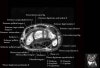

- Axial section

Axial PD fat suppressed evaluates the tendons of the wrist and carpal tunnel, including the median nerve.